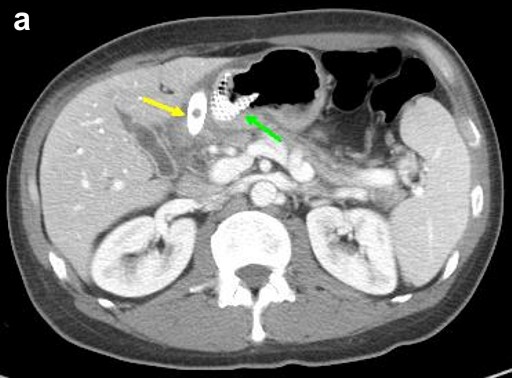

Thus, EUS-guided transduodenal biliary drainage (EUSBD) was performed. A linear array echoendoscope (GF-UCT140, Olympus America, Center Valley, PA, USA) was placed in the duodenal bulb allowing visualization of a dilated common bile duct (Figure 1). A 19-gauge FNA needle (Wilson-Cook Endoscopy, Winston-Salem, NC, USA) was used to perform a transduodenal puncture of the common bile duct through the proximal end of the duodenal stent. Bile was aspirated and a cholangiogram demonstrated good filling of the right and left duct systems with no evidence of a stricture proximal to the puncture site (Figure 2). Under fluoroscopy, a 0.035-inch straight guidewire (Jagwire, Boston Scientific Corporation, Natick, MA, USA) was passed into the biliary tree and directed toward the hilum. The FNA needle was exchanged for a biliary dilating balloon (Hurricane RX, Boston Scientific Corporation, Natick, MA, USA). The choledochoduodenostomy tract was dilated to 6 mm. A 10x60 mm fully covered self-expanding metal biliary stent (Wallfex®, Boston Scientific Corporation, Natick, MA, USA) was placed over the guidewire and deployed under fluoroscopy. One cm of the stent was left protruding into the duodenal bulb through the mesh at the proximal end of the duodenal stent (Figure 3). Good bile and contrast efflux was seen. The final fluoroscopic image did not demonstrate a bile leak (Figure 4). Post-procedure CT imaging demonstrated good positioning of the biliary stent and no evidence of a bile leak (Figure 5).

Figure 5. Post-procedure CT demonstrating: a. juxtaposition of metal biliary (yellow arrow) and duodenal (green arrow) stents with no evidence of a bile leak; b. fully covered metal biliary stent (yellow arrow) terminating in the common bile duct; c. no evidence of pelvic ascites to suggest a bile leak. |